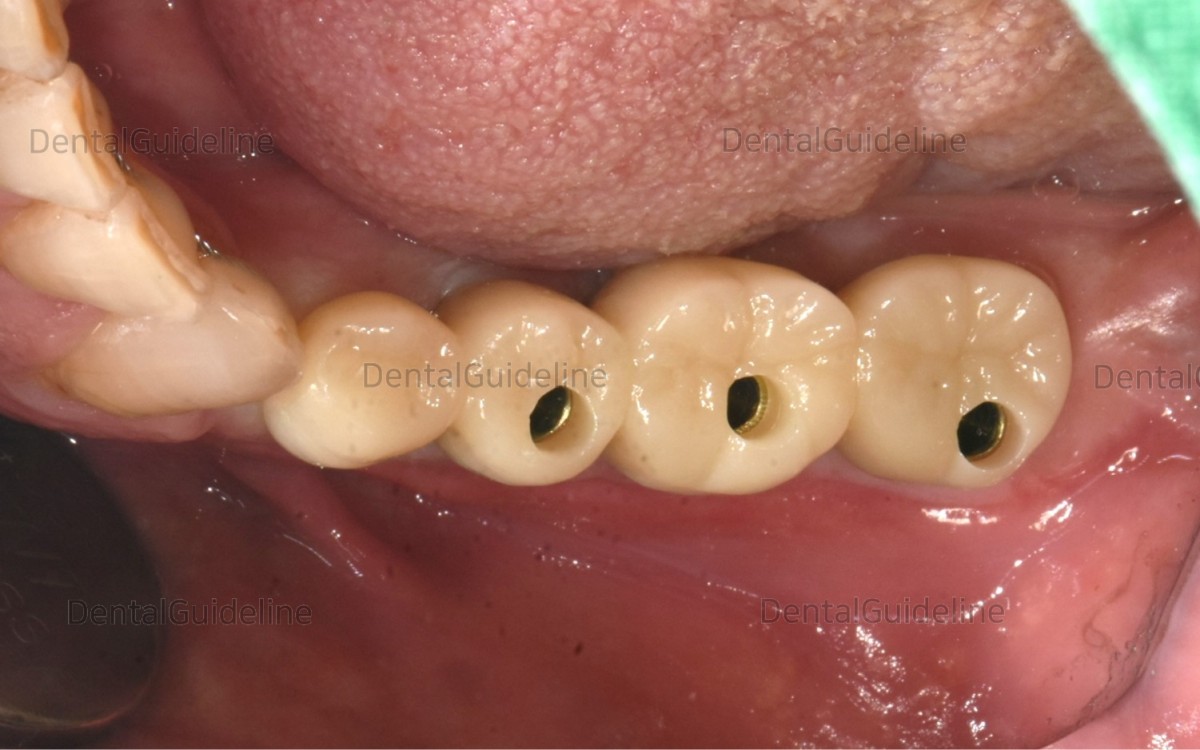

Intraoral

view shows the healing status of post-op 7 weeks.![]()

The restoration was seated onto the abutment.

The restoration was cemented permanently and the access hole was filled with composite resin.